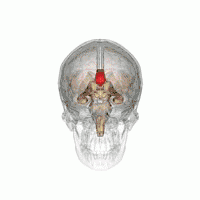

الجسم الثفني أو الصوار الثَفَني (بالإنجليزية: Corpus Callosum) هو حزمة مسطحة واسعة من الألياف العصبية بيضاء اللون تحت القشرة في الشق الطولي للدماغ، تمتد عدة سنتيمترات من الأمام إلى الخلف، وهو أكبر هيكل من المادة البيضاء في الدماغ، ويتكون من ملايين الألياف العصبية التي تربط بين النصفين الكرويين الأيمن والأيسر في الدماغ ويسهل الإتصال بينهما، وتنتقل المعلومات بينهما على هيئة إشارات كهربائية، ولذلك أيضاً يُعرف باسم "المُقْرِن الأعظم".[1] وهو أكبر بنية للمادة البيضاء في الدماغ، يحتوي على 200-250 مليون نتوءات محوارية عصبية مقابلة.

يسمى الجزء الخلفي من الجسم الثفني بالشريط؛ الجزء الأمامي يسمى الركبة؛ بين الجزئين ما يسمى بالجذع، أو "الجسم". غالباً الجزء بين الجذع والشريط ضيق بشكل ملحوظ وبالتالي يشار إليه ب "البرزخ". المنقار هو جزء من الجسم الثفني الذي يبرز للخلف وللأسفل من أكثر جزء أمامي للركبة، كما يمكن مشاهدته على الصورة السهمية للدماغ المعروضة على اليسار. المنقار سمي بذلك لأنه يشبه منقار الطائر. على كل جانب من الجسم الثفني، تنتشر الألياف في المادة البيضاء وتمر إلى مختلف أجزاء قشرة المخ؛ الألياف المنحنية للأمام من الركبة إلى الفص الأمامي تشكل الملقط الأمامي، والألياف المنحنية للخلف إلى الفص القذالي تشكل الملقط الخلفي. بين الملقط الأمامي والخلفي يكون الجزء الرئيسي من الألياف الذي يشكل البساط ويمتد جانبياً على الجهتين إلى الفص الصدغي، ويغطي الجزء الأوسط من البطين الجانبي. محاور عصبية رفيعة في الركبة تربط القشرة أمام الجبهية بين نصفي الدماغ؛ هذه الألياف تنبثق من حزمة من الألياف تشبه الشوكة من البساط، الملقط الأمامي. المحاور العصبية الأثخن في منتصف الجسم الثّفَني أو في جذع الجسم الثفني، تربط مناطق القشرة الحركية، وبتناسب الكثير من الجسم الثفني المكرس بشكل إضافي للمناطق الحركية بما في ذلك باحة بروكا. الجزء الخلفي من الجسم الثّفَني؛ المعروف بالشريط، ينقل معلومات حسية جسدية بين نصفي الفص الجداري والقشرة البصرية في الفص القذالي، هذه هي ألياف الملقط الأمامي.[2][3]